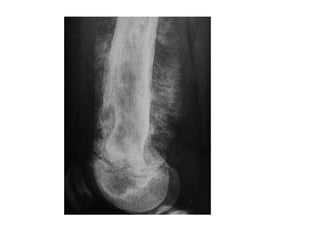

A lateral radiograph of a surgical

specimen of a myxoma

An occlusal view shows

buccal expansion

1- Odontogenicmyxoma

Od. Myxoma

Multilocular (Soap bubble > Tennis-racket)

Pericoronal to unerupted tooth or from a tooth that failed to develop

• 2nd- 3rd decade, ♀

• Mand. > Max. Molar – premolar.

• Discovered while searching for the cause of unerupted tooth

• Identified upon:

-Grows along the bone, lees likely to expand

-Grows around teeth causing scalloping, loosening, displacement of teeth but

rarely resorption

Multilocular

• Radiography:

• Typically appears as multi

locular radiolucent area

with well defined scalloped

margin or soap bubble.